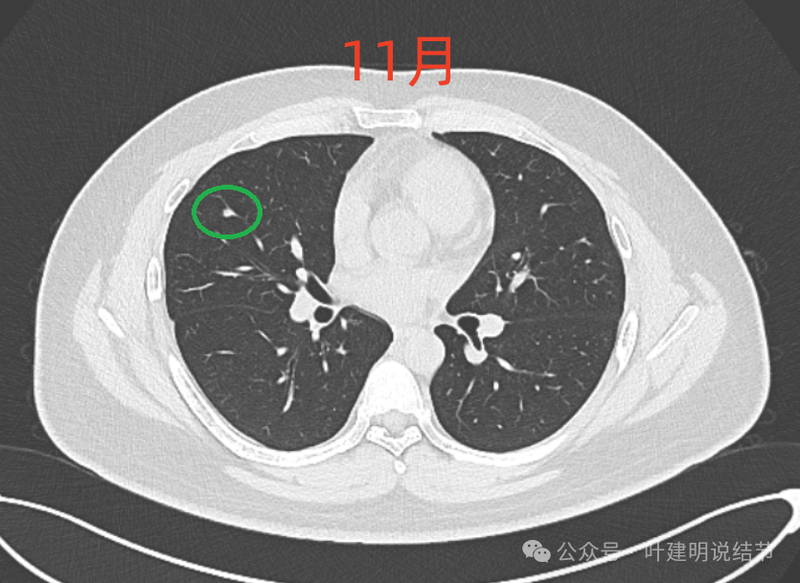

病灶4:

左下磨玻璃微小结节,轮廓与边界清楚,像是肿瘤范畴的,肺泡上皮增生或不典型增生可能性大,近期风险小。

8月时与后来的相仿。

现在的人工智能辅助诊断系统太过敏感,非常微小的结节都给你找出来,但是对于临床来说并没有多大意义。当结节才几个毫米的时候,既没有办法明确到底是什么,也没有必要明确到底是什么,按照中华医学会肺癌诊疗指南,8毫米以下纯磨玻璃结节或5毫米以下实性结节(包括混合密度结节实性成分不足5毫米)也就是年度复查就可以。所以其实并不一定要在意到底有多少处结节,或者要考虑是什么。主要就关注最主要的病灶,如果主病灶仍没有风险可以年度体检复查,那就可以随访,不能也不必有过大的思想顾虑。我看了你的CT,目前这些结节均风险小,其中右侧桔色框起来的是所谓主病灶,仍是纯磨密度,又还小,考虑不典型增生可能性较大;左下桔色的也是磨玻璃密度,但轮廓不如右上这处清楚,若确实肿瘤范畴,也是原位癌或不典型增生可能性大,但也有少许慢性炎伴肺泡上皮增生或纤维增生的可能性;中叶绿色的密度过高,更符合良性些;右下黄色的过小,11月份的像磨玻璃密度,边界较清,但对比8月时的,此灶不太明显,当然本身过小,也可能没有扫到最明显层面,不过总归风险小,能观察随访(左下的也8月时更显淡和不明显点)。总体上,这几处病灶都是风险还低,可以继续半年到一年复查随访,真若有明显进展并具有一定的风险再来干预处理不影响预后。本身年纪轻,又是多发结节,目前的病灶又都风险低,可以过于积极赶紧处理。意见供参考!